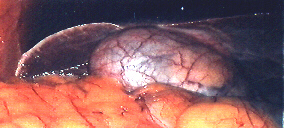

Galloedem.jpg (42318 Byte)Laparoskopsiches Bild akute Cholecystitis

ist in aller Regel systemisch geschwächt, er hat Fieber, ist mitbedingt durch die lokale Peritonitis (Bauchfellentzündung) cardiopulmonal insuffizient (von Seiten der Atmung und des Kreislaufs geschwächt), aufgrund der Entzündung besteht eine erhöhte Blutungsneigung.